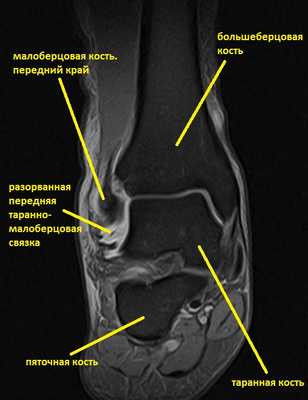

Ниже представлены срезы МРТ в которых наглядно показано расположение повреждённых связочных структур.

Данные повреждения практически в 100 % случаев пропускаются при первичном обращении в травмпункт. При несвоевременном или неадекватном лечении нестабильность голеностопного сустава приводит к разрушению суставного хряща, выраженной боли, деформации, и в конечном счёте к полной утрате функции опоры и ходьбы. В зависимости от того какие связки разорваны и от того насколько выражена нестабильность, артроз развивается в разные сроки, от 1 года при разрыве синдесмоза, до 20 и более лет при изолированном разрыве передней таранно-малоберцовой связки.

На этом этапе пациентка лечилась по стандартному сценарию «растяжение голеностопа». Носила ортез, мазала голеностоп вольтареном и лиотоном, разгружала его при помощи трости. Но в связи с длительно сохраняющимся болевым синдромом было выполнено МРТ, при котором диагностирован застарелый разрыв передней таранно-малоберцовой связки, пяточно-малоберцовой связки правого голеностопного сустава, контузионное повреждение латеральных отделов таранной кости.